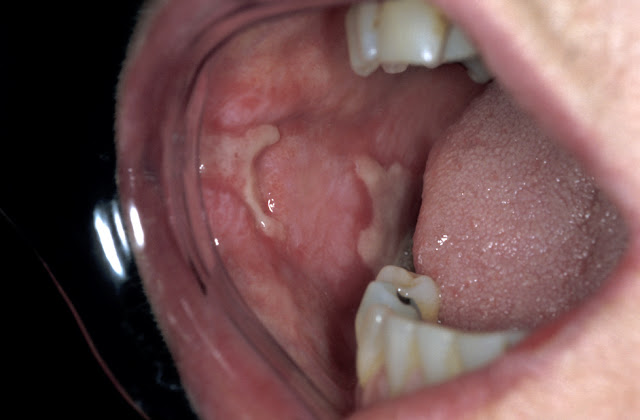

2/ Các tổn thương niêm mạc miệng khác do thuốc lá:

(Bệnh nhân bị tổn thương niêm mạc, khó chịu khi ăn uống)

Viêm miệng do nicotine (nicotinic stomatitis): Là một sự thay đổi ở niêm mạc vòm miệng cứng do hút thuốc quá nhiều, niêm mạc vòm miệng trở nên trắng với các u nhỏ gồ lên, trên đó có các chấm đỏ. Tổn thương này sẽ mất đi sau khi dừng thuốc lá, một số trường hợp hiếm trở thành ung thư biểu mô.